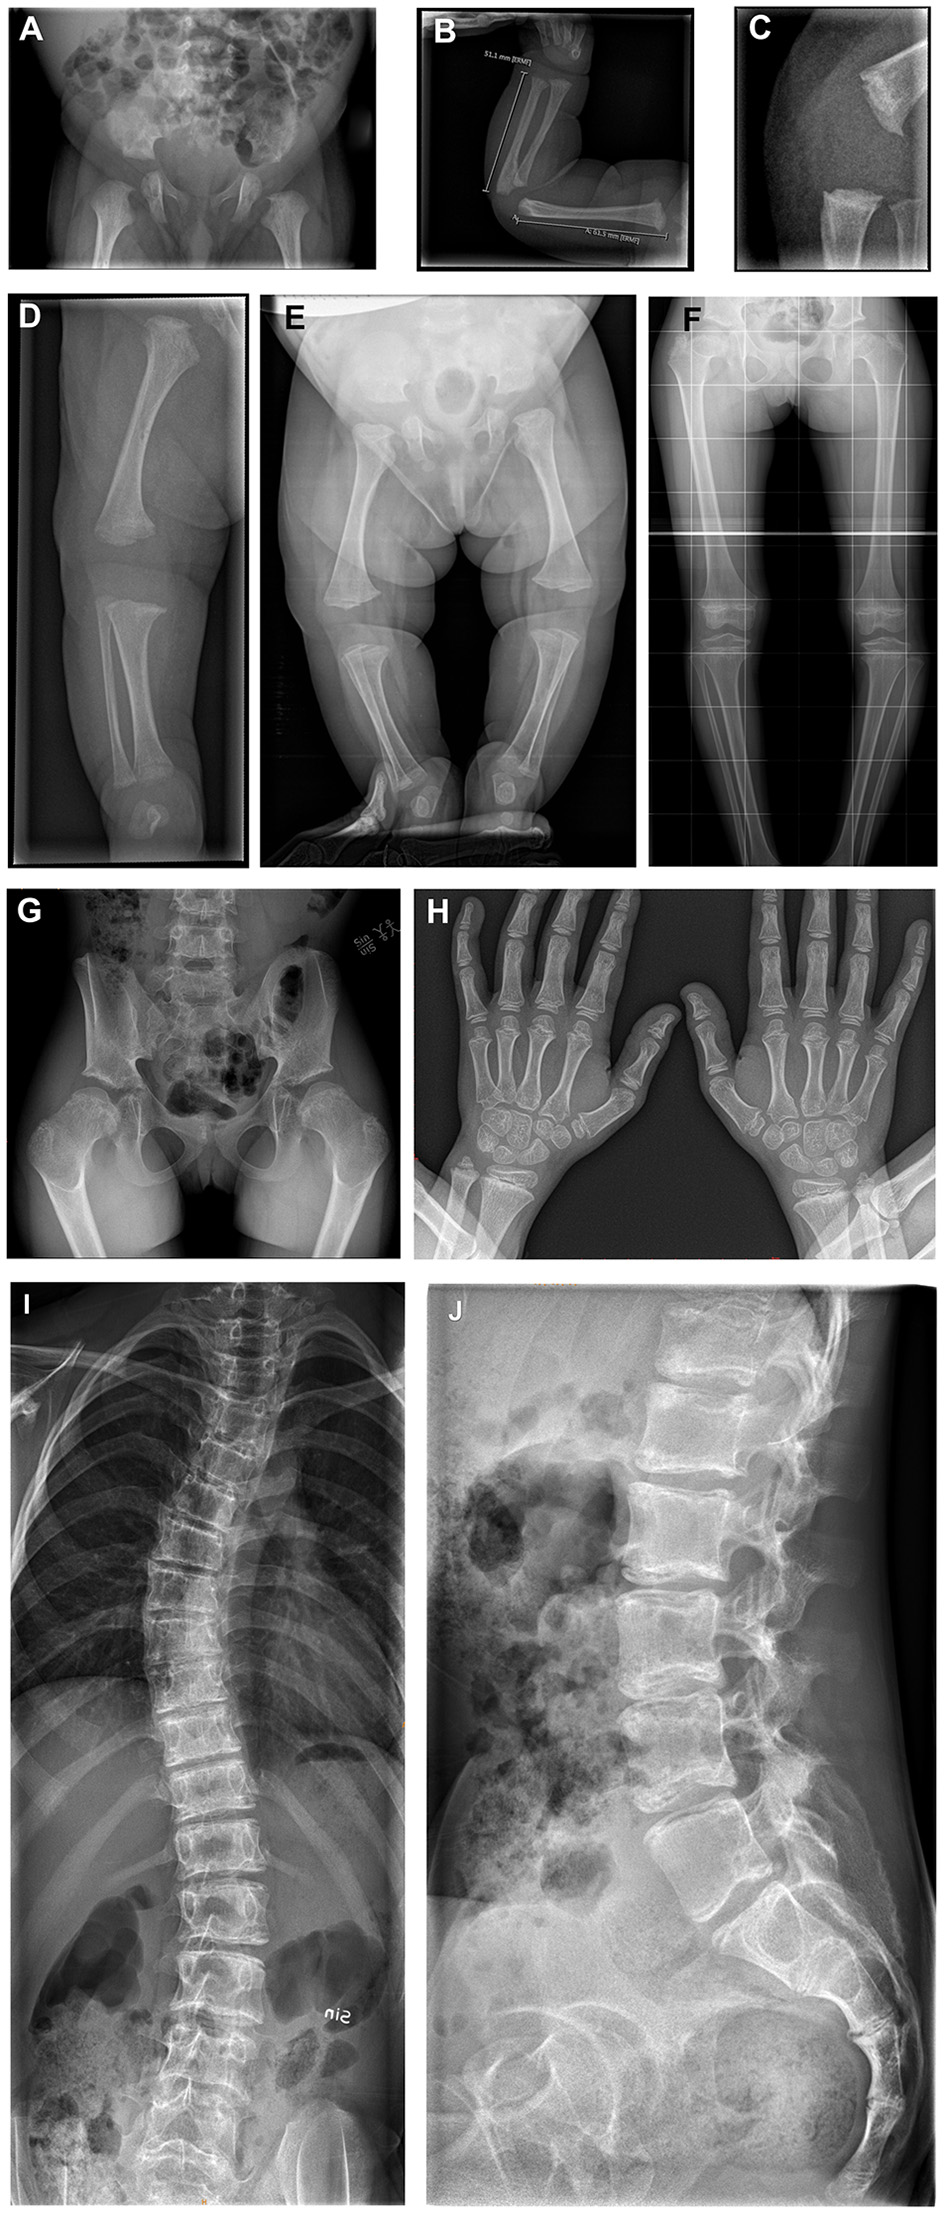

Bones

Short limbs were found on clinical examination in eight of nine patients (89%). Skeletal malformations such as trunk–limb disproportion, coxa vara, and scoliosis had been reported in the first NANS-CDG case series (5). Indeed, skeletal malformations were present in all eight currently reported patients for whom radiographic imaging was available (Figure 4):

-

Skull: frontal bossing (n = 2/2; 100%).

Spine: spinal deformities (n = 5/6; 83%), vertebral sclerosis (n = 2/6; 33%), less/irregular calcification of vertebral plates (n = 2/6; 33%); abnormal vertebral plates with sclerosis (n = 2/6; 33%) and abnormal ossification centers (n = 1/6; 17%).

Pelvis: short femoral neck (n = 5/5; 100%), small femoral head (n = 4/5; 80%), small iliac wings (n = 3/5; 60%), flat/dysplastic acetabula (n = 3/5; 60%), sclerosis of iliac crest (n = 1/5; 25%), and luxated hip (n = 1/5; 25%).

Upper extremities: metaphyseal widening (n = 7/8; 88%), metaphyseal sclerosis (n = 6/8; 75%), metaphyseal irregularity (n = 5/8; 63%), and small epiphyses (n = 2/8; 25%).

Lower extremities: metaphyseal sclerosis (n = 5/6; 83%), metaphyseal widening (n = 4/6; 67%), metaphyseal irregularity (n = 3/6; 50%), small epiphysis (n = 2/6; 33%), dysplastic knee joints (n = 1/6; 17%), genu vara (n = 1/6; 17%), fibular overgrowth (n = 1/6; 17%), and sclerosing knee metaphysis (n = 1/6; 17%).

Figure 4

(A) X-rays of the skeleton of patients 3, 4, and 6. (A–D) Patient 3 at age 4 days; born with multiple congenital abnormalities of the bones. (A) The pelvis shows flat acetabula and short femoral necks. (B) The right arm demonstrates metaphyseal widening and irregularity. (C) The knee in the lateral view demonstrates metaphyseal irregularity in detail. (D) The image of the right leg demonstrates irregularly widened metaphyses at the distal femur and proximal and distal tibia, with a dysplastic knee joint and varus deformity. (E) Patient 4 at age 4 months; total legs, demonstrating flat acetubular roofs, wide femoral head metaphyses with short femoral necks. There is slight bowing and varus in the knees. The metaphyses around the knee show widening and irregularity. (F–H) Patient 6 at age 7 years. (F,G) Total legs and pelvic showing small iliac wings, coxa vara with small femoral heads and necks. This is shown in detail in image (G). The metaphyses around the knee demonstrate the typical striated sclerosis. The knee joints are dysplastic, and there is a varus deformity. (H) Both hands with irregularly widened and sclerotic metaphyses in the distal radius and ulna. Irregular metaphyses of the phalanges. (I,J) Patient 6 at age 12 years; total spine with scoliosis. The vertebral plates seem to have a double layer, with abnormal sclerosis of the plates. Lateral view shows the sclerosing of the vertebral plates from dorsal to ventral, resulting in a double contour.